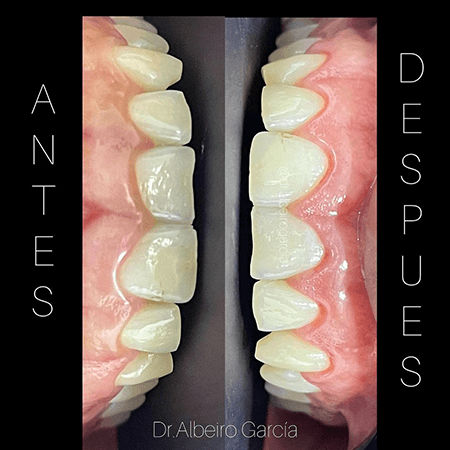

Dr. Albeiro García Varela

Odontólogo Santa Marta

Antes y después de tratamiento para el alargamiento de encía

Dr. Albeiro García Varela

Odontólogo Santa Marta

Gingivectomía realizada por el odontólogo Albeiro Garcia de Santa Marta